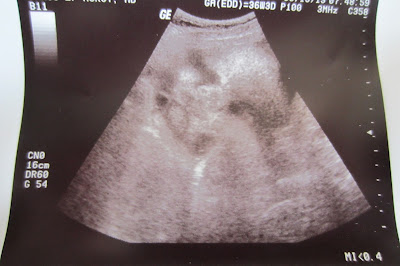

Baby boy - we are officially FULL TERM!

We got to see you on the ultrasound and you were nice and squished. :) We immediately saw your cute little face and the nurse said, "He already has chubby cheeks". We measured you and you are around 7 lbs. I guess we'll see if you hit the 9 lb mark like your brother and sister!